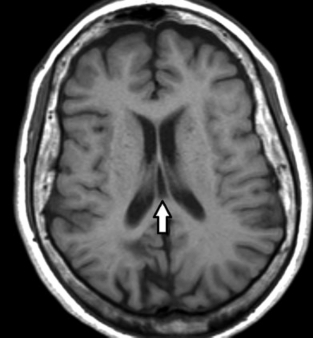

Constituyen variantes anatómicas que se presentan en la línea media derivando de alteraciones del desarrollo del septum pellucidum (SP).7 En TC y RM se los aprecia con densidad o señal similar al LCR (►Figs. 1, 2, 3).7

RM de cerebro, corte axial ponderado en T1. Se señala (flecha) la presencia de una cavidad triangular cefálica al trígono, compatible con cavum del velo interpósito (CVI).